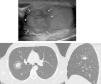

Presentamos el caso de un varón de 29años que consulta por palpación de lesión indurada en el testículo derecho. Se realiza un estudio ecográfico que se informa como alteración pseudonodular de la ecoestructura testicular, compatible con tumor testicular (fig. 1A, flechas). Se decide completar el estudio con una TC toracoabdominal para realizar estudio de extensión, visualizándose un nódulo pulmonar único, localizado en el lóbulo superior derecho, que presentaba un halo en vidrio deslustrado periférico compatible con metástasis hemorrágica (fig. 1B,C). El paciente fue sometido a una orquiectomía, y el estudio histológico reveló que se trataba de un seminoma anaplásico con componente de coriocarcinoma.

El signo del halo en la TC es un signo poco específico que se asocia a entidades como aspergilosis, candidiasis, tuberculoma con síntomas de hemoptisis, linfoma o carcinoma broncoalveolar1. Se reconoce en la TC al visualizar un nódulo denso con halo periférico en vidrio deslustrado2. Los angiosarcomas y los coriocarcinomas, como en nuestro caso, son los tumores que más frecuentemente lo producen.